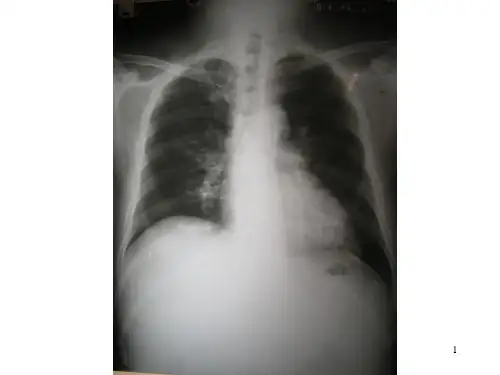

(三)胸部影像学检查。发生肺炎的患者肺内出现片 状阴影。重症患者病变进展迅速,常呈双肺多发磨玻 璃影及肺实变影像,可合并少量胸腔积液。发生ARDS 时,病变分布广泛。

(一)病变早期。在发病2天内肺部即可出现病变影像, 早期多为小片状影,呈单发或多发。病变以磨玻璃密 度影为主,可合并肺实变影像。片状影分布在双侧肺 或主要位于一侧肺。